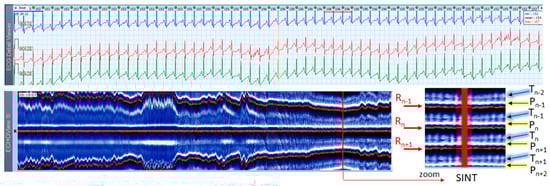

3.3. Sinus Tachycardia Cases

This section interprets together 3-lead Holter ECG strips and the corresponding ECHOView images (ECG lead 1) of three patients with SINT (Figure 6, Figure 7 and Figure 8). When the HR is too high, it is sometimes difficult to differentiate true SINT, caused by a physiological increase in the sinoatrial node activity from SVTs due to re-entry circuits, increased focal atrial automaticity, or triggered activity. The examples below represent somewhat complex cases from an ECG diagnostic perspective, where SINT mimics atrioventricular reentrant tachycardia (AVRT) (Figure 6), or focal atrial tachycardia, atrioventricular nodal reentrant tachycardia (AVRNT) (Figure 8), AFL with AV conduction 2:1 (Figure 6 and Figure 8) or atrial tachycardia (Figure 7). The general difficulty is the recognition of the sinus P-wave at high cardiac rates, particularly in Holter ECG strips recorded with less number of channels than the standard 12-lead ECG (usually made at rest, when sinus tachycardia is not so common). As shown in one-lead ECHOView images below, the sinus P-wave band in SINT is well seen as a blue-white band. In the three examples, it maintains a constant distance from the red band of the central R-peak, which stands for a stable PR-interval, regardless of beat-by-beat RR-interval change. The latter is well seen in the ECHOView images by three horizontal red traces for three sequential R-peaks, presenting useful information on the long-term HR variation in SINT, which demonstrates patient-specific dynamics in the three examples.

4.3. ECHOView: Summary of the Principles of Imaging

The color-coded ECG amplitudes of sequential beats produce an intuitive trace of different intervals (PnRn, RnTn, Rn−1Rn, RnRn+1, etc.) in a visible image (width × height = 1740 beats × 1500 ms) within one ECHOView page. Without a specific measurement, this visual effect resembles the rendering of one-dimensional time trends of automatically measured ECG intervals. These trends show stable PnRn and RnTn intervals during the NSR part of the examples in Figure 4, Figure 5, Figure 6, Figure 7, Figure 8, Figure 9, Figure 10, Figure 11 and Figure 12. The trends are also informative for the RR-intervals (Rn−1Rn, RnRn+1) on a beat-by-beat basis that is helpful for identifying long-term HR changes in high-rate SINT (Figure 6, Figure 7 and Figure 8) and AFL (Figure 15), as well as rhythm, transitions NSR→ paroxysmal SVA (Figure 9), NSR→PSVT (Figure 10, Figure 11 and Figure 12), NSR→NSVT (Figure 10, Figure 11 and Figure 12), and AF→AFL→ST (Figure 16).